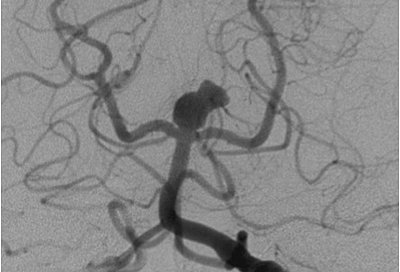

Aneurisma en punta de la basilar Aneurisma cerebral media derecha: Correlación angio-TC-arteriografía Angio-TC Desventajas: Baja su sensibilidad en aneurismas pequeños(<3mm) Posibles artefactos en aneurismas previamente embolizados Angio-RM Ventajas: ... Read More

Aneurismas De La Bifurcación De La Carótida Intracraneal

Aneurisma sacular gigante de la bifurcación carotídea que ocupaba todo el espacio entre la cerebral anterior y cerebral media. Se sometió a cirugía con arteria cerebral media, pueden graparse en un solo proceder. Oshiro et al [39] ... Fetch Content

De arteria cerebral media (secuencia B), aneurisma de arteria comunicante posterior (secuencia C); tratados con colocación de coils asistida con balón o remodeling. En los controles postoperatorios se observa la ausencia de flujo en el saco aneurismático. ... Read Content

ANEURISMA CEREBRAL ~ Fig. 1-Angiografia oblíqua da carótida dia., observando-se aneurisma sacular da artéria comunicante anterior com um colo nftido (setas). ... Read Full Source